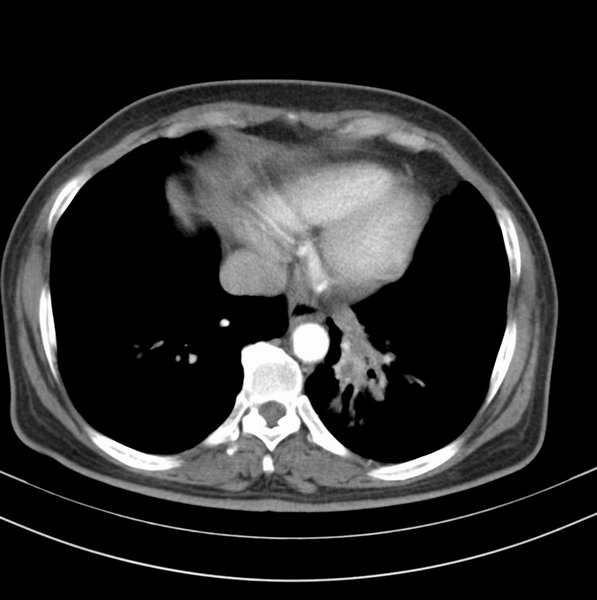

女、63

咳嗽、胸痛四个月

考虑左下肺中央型肺癌

支持左下中央型肺癌伴阻塞性炎症不张。

包绕左下肺基底段的不规则的软组织肿块,段支气管腔变形、狭窄及阻塞性炎症,病变区不规则强化,又是老年女性支持楼上看法。

典型病例:左下肺基底段中央型肺癌,相应支气管狭窄并阻塞性炎症